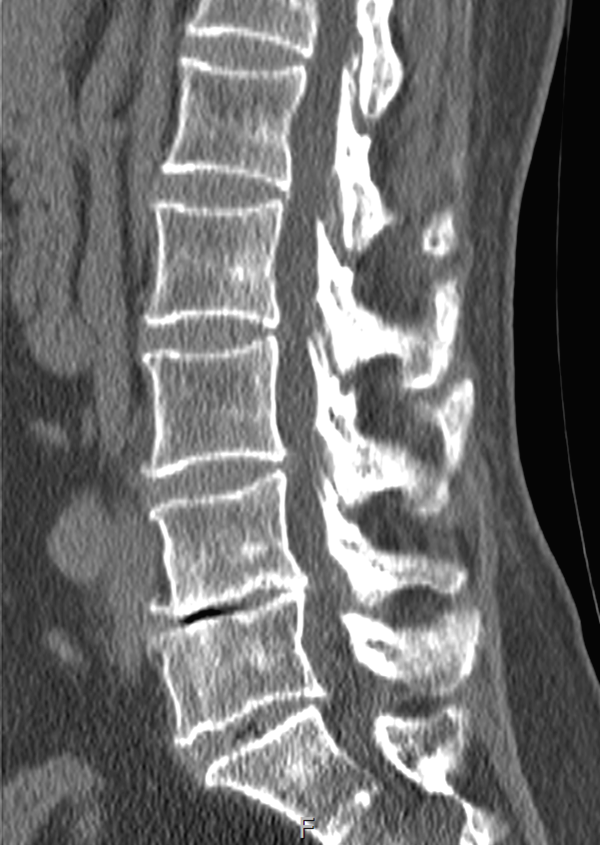

CT (컴퓨터 단층촬영)

뼈와 주변 연부 조직 동시 확인

금속 이식물 있는 분들께 특히 유용

디스크 상태 완벽 진단은 어려워요